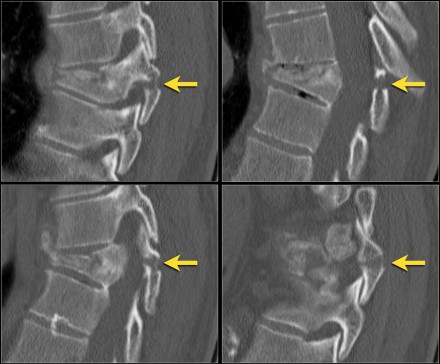

Scroll through the images.

How would you describe the morphology and the PLC?

The findings are:

- The morphology is burst (2 points)

- The PLC is injured with a fracture through the adjacent spinous processes. One of the fractures is a typical avulsion.

- TLICS score: 5 points

You could argue that these fractures of the spinous processes indicate distraction, i.e. 4 points for morphology.

However in this case the compression is the most prominent finding.